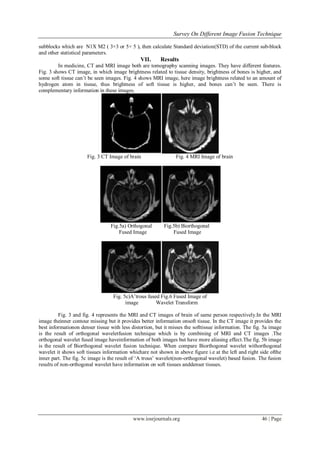

In medicine, CT and MRI image both are tomography scanning images. They have different features.

Fig. 3 shows CT image, in which image brightness related to tissue density, brightness of bones is higher, and

some soft tissue can’t be seen images. Fig. 4 shows MRI image, here image brightness related to an amount of

hydrogen atom in tissue, thus brightness of soft tissue is higher, and bones can’t be seen. There is

complementary information in these images.

Fig. 3 CT Image of brain Fig. 4 MRI Image of brain

Fig. 3 and fig. 4 represents the MRI and CT images of brain of same person respectively.In the MRI

image theinner contour missing but it provides better information onsoft tissue. In the CT image it provides the

best informationon denser tissue with less distortion, but it misses the softtissue information. The fig. 5a image

is the result of orthogonal waveletfusion technique which is by combining of MRI and CT images .The

orthogonal wavelet fused image haveinformation of both images but have more aliasing effect.The fig. 5b image

is the result of Biorthogonal wavelet fusion technique. When compare Biorthogonal wavelet withorthogonal

wavelet it shows soft tissues information whichare not shown in above figure i.e at the left and right side ofthe

inner part. The fig. 5c image is the result of ‘A trous’ wavelet(non-orthogonal wavelet) based fusion. The fusion

results of non-orthogonal wavelet have information on soft tissues anddenser tissues.